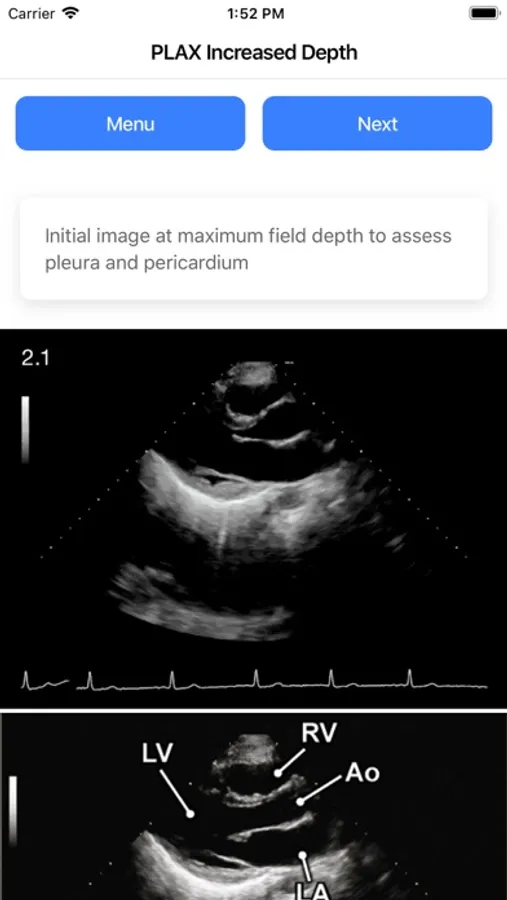

The second feature is imaging protocols. Currently I have included a Comprehensive TTE protocol (from London Health Sciences Centre Echo Lab) with linked graphics, echo videos, and acquisition guide sourced from the respective ASE guideline. This should serve as a great reference for most Cardiology trainees starting an echo rotation or as a quick reference on call. I have also updated the app with POCUS (Cardiac, TEE, and Lung) protocols.